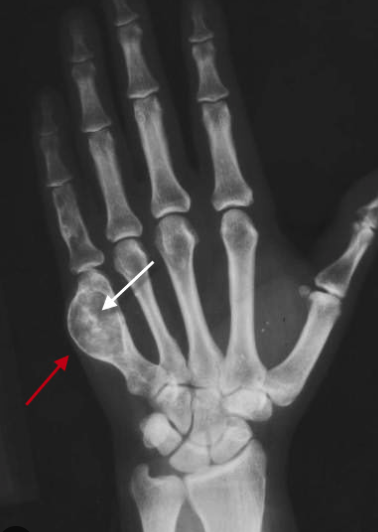

16

Enchondroma

The ARCS AND RINGS is the more classic textbook look with the irregularly speckled calcification of chondroid matrix

Just like fibrous dysplasia, classic matrix is not found in the fingers or toes

the most common cystic lesion in the hands and feet